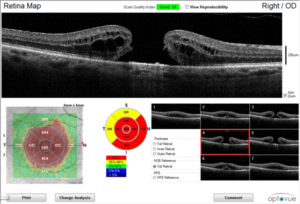

OCT image showing a macular hole